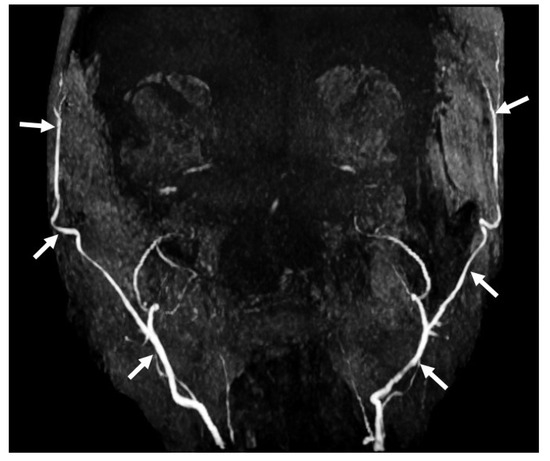

7.8. Magnetic Resonance Angiography (MRA) Brain